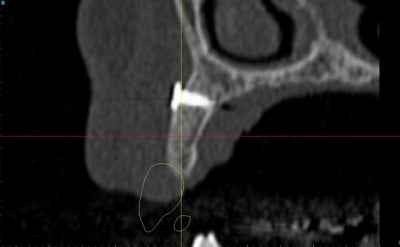

dentiste57 écrivait:

--------------------

> et là ?

> greffe selon ta méthode ?

Cross section dhvkc8 - Eugenol

3d dt3qom - Eugenol

Overview uqcp6u - Eugenol

S2y2o1v7q53ws4r5wy6ou8czrpom - Eugenol

pxav

01/05/2011 à 12h55

> dentiste57 écrivait:

> --------------------

> > et là ?

> > greffe selon ta méthode ?

expansion, c'est plus cool!